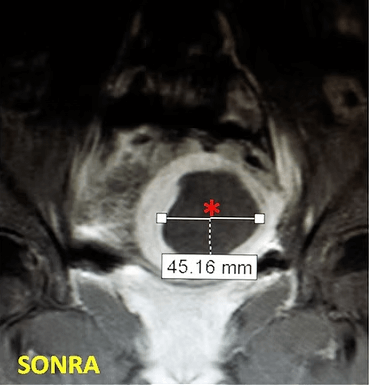

29 yaşında, adet uzaması, kansızlık ve sık idrara çıkma şikayetleri olan ve daha önce 2 kez miyomektomi olan hasta. Emar’da idrar kesesine bası yapan 85mm çaplı miyom (*) mevcut. Embolizasyondan sonra miyomun öldüğü ve küçüldüğü izleniyor. 7 ay sonra hasta şikayeti kalmamış ve 4 yıllık takip süresince yeni miyom oluşmamıştır.